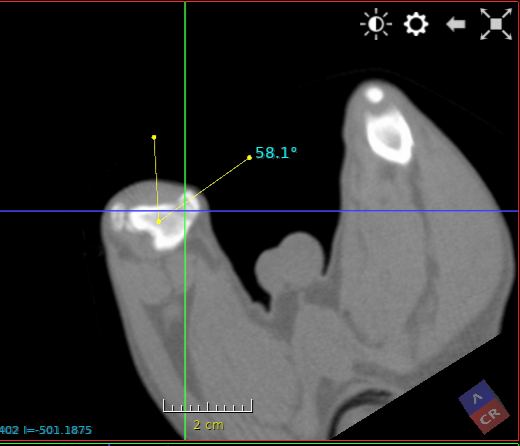

keeshond van 5 maanden met een  ernstige patella luxatie . De knieschijf zit permanent aan de binnenzijde van de knie. Het onderbeen heeft een torsie van 58.1 graden ten opzichte van het bovenbeen. Het bovenbeen heeft een kanteling van 29 graden ten opzichte van het kniegewricht.

De scan beelden zijn gebruikt om een operatieve ingreep voor te bereiden.